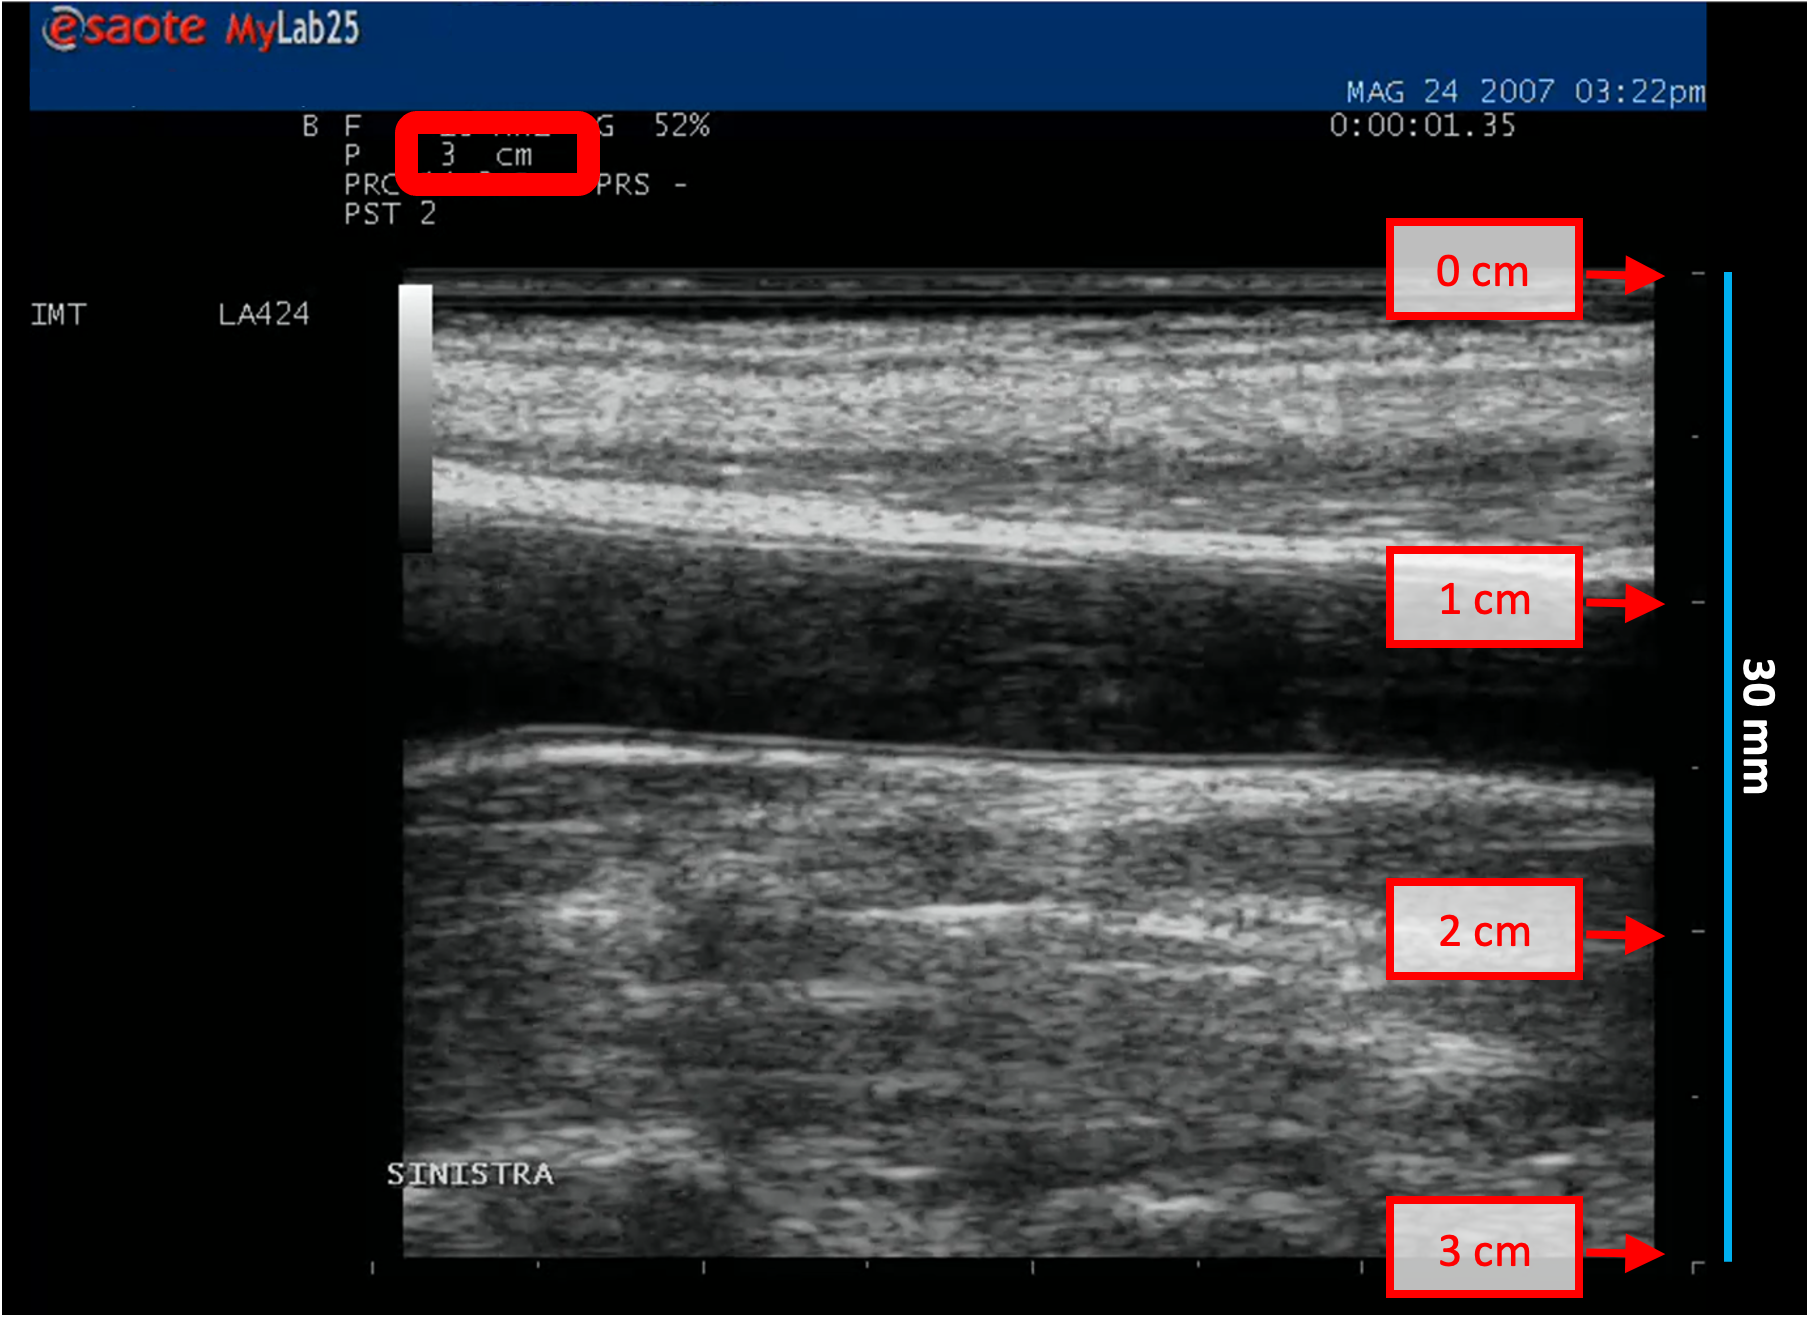

• Locate, in ultrasound image, a range of known distance (30 mm in the example of figure).

B-mode calibration examples

The following images show examples of calibrations of the b-mode image. Graphic items in red shows where you can find the information about the depth of the image in the ultrasound image.